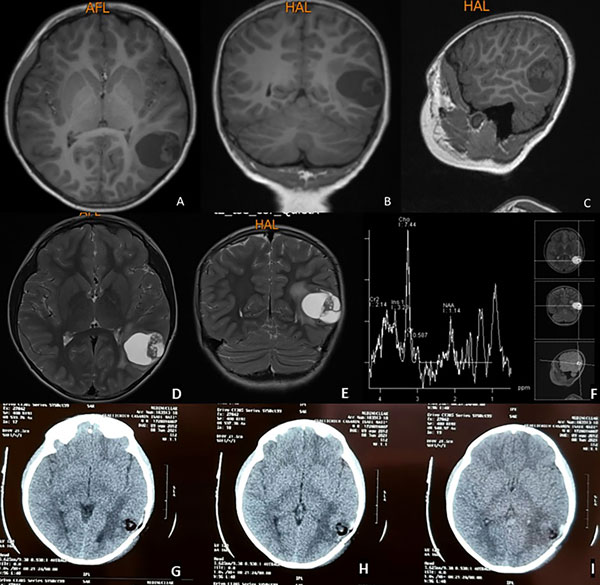

Paciente masculino de 8 años sin antecedentes patológicos conocidos, con crisis convulsivas tonicoclónicas generalizadas de 20 segundos de duración, sin presencia de aura ni relajación de esfínteres (estado postictal de 1 minuto y recuperación completa) de 2 meses de evolución. En un inicio los episodios tenían una frecuencia de 2 por semana, para alcanzar en los últimos 15 días 4 crisis diarias. A la consulta se indica levetiracetam con buena respuesta y se realiza resonancia magnética que evidencia lesión intraaxial temporal izquierda quística, hipointensa en T1 e hiperintensa en T2 y FLAIR con nódulo en su interior. La lesión mide aproximadamente 4 cm de diámetro mayor con escaso edema perilesional y moderado efecto de masa, sin herniación subfalcial y cisternas de la base visibles. La espectroscopia demostró presencia de picos de colina (Figura 1).

Figura 1. Resonancia magnética simple en secuencia T1. Se evidencia lesión ocupativa de espacio intraaxial temporal izquierda, quística, corticosubcortical hipointensa. A) Corte axial. B) Corte coronal. C) Corte sagital. En secuencias T2: D) Corte axial E) Corte coronal. F) Espectroscopía cerebral con pico de colina. G, H, I) Tomografía axial computarizada postquirúrgica: se evidencia estigma de craneotomía temporal izquierda, resección tumoral completa, lecho tumoral sin sangrado con material de hemostasia, escaso neumoencéfalo y moderado edema vasogénico.